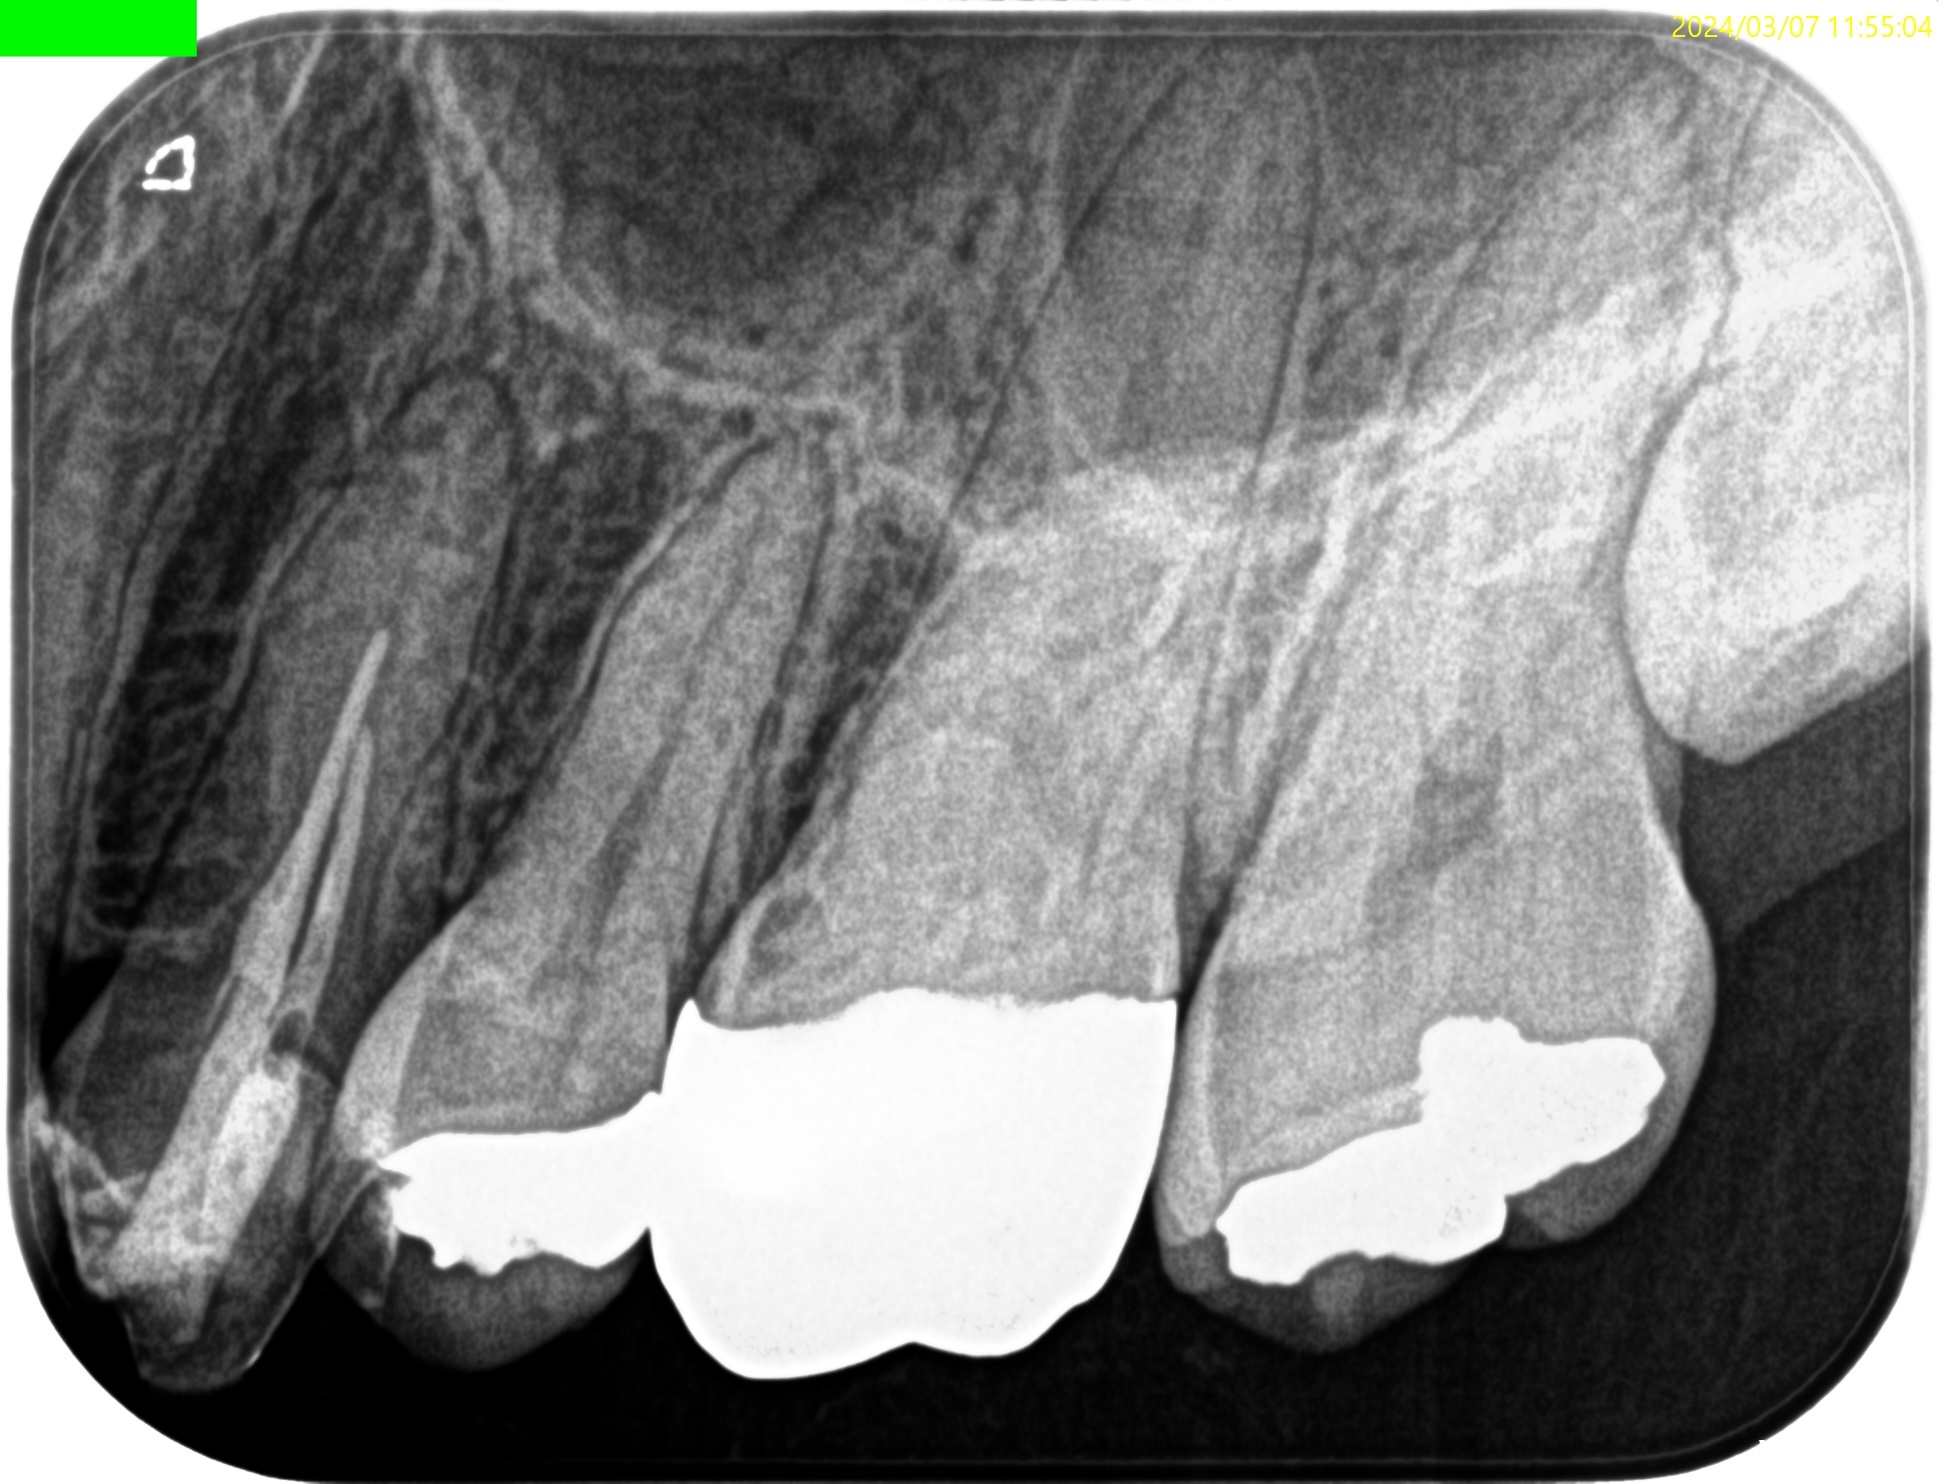

#12 Apicoectomy(2025.3.7)

Apexの位置のOsteotomyすると、そのApexは容易に発見できた。

根尖を3mm切断し、メチレンブルーで染色した。

問題はない。

逆根管形成し、逆根管充填した。

ペントロンジャパンの

エンドセム MTA クイックペースト R

で逆根管充填した。

いわゆるシーラー逆根管充填(そんな言葉があるのか?)である。

術後にPA, CBCTを撮影した。